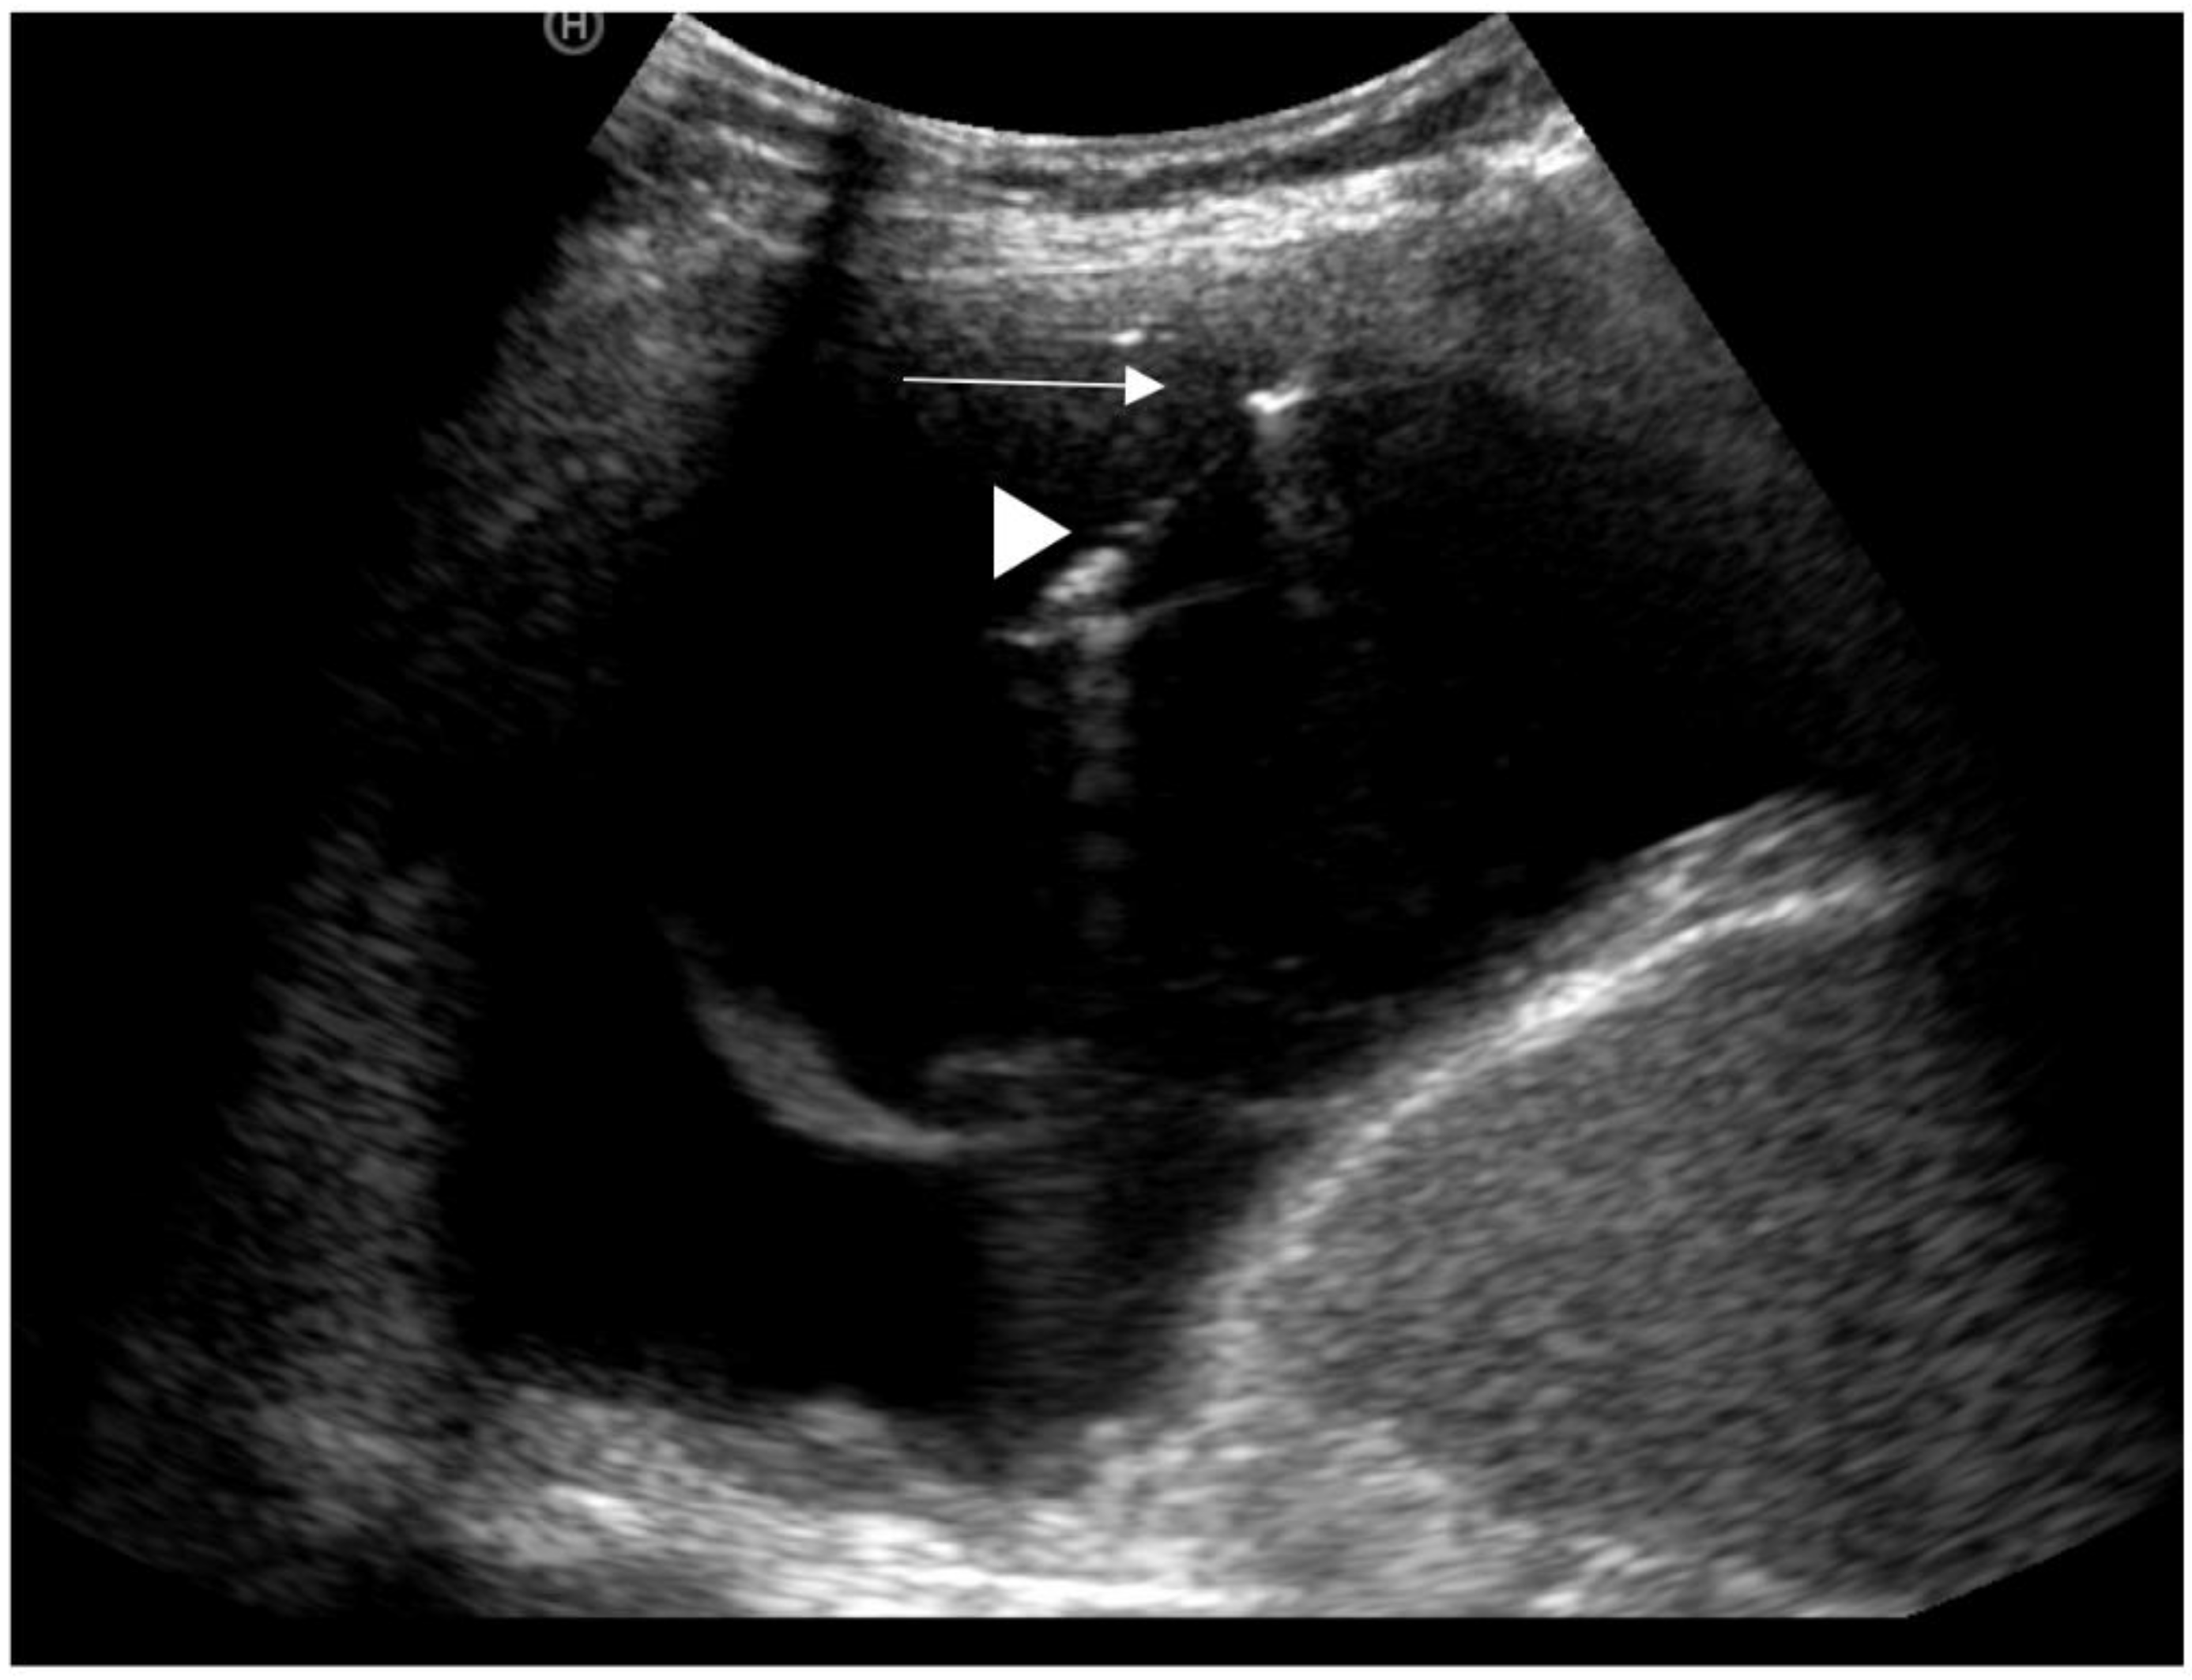

13. Ultrasound

- Yang, P.C.; Luh, K.T.; Chang, D.B.; Wu, H.D.; Yu, C.J.; Kuo, S.-H. Value of sonography in determining the nature of pleural effusion: Analysis of 320 cases. Am. J. Roentgenol. 1992, 159, 29–33. [Google Scholar] [CrossRef]

- Asciak, R.; Hassan, M.; Mercer, R.M.; Hallifax, R.J.; Wrightson, J.M.; Psallidas, I.; Rahman, N.M. Prospective Analysis of the Predictive Value of Sonographic Pleural Fluid Echogenicity for the Diagnosis of Exudative Effusion. Respiration 2019, 97, 451–456. [Google Scholar] [CrossRef]

- Chen, H.-J.; Tu, C.-Y.; Ling, S.-J.; Chen, W.; Chiu, K.-L.; Hsia, T.-C.; Shih, C.-M.; Hsu, W.-H. Sonographic Appearances in Transudative Pleural Effusions: Not Always an Anechoic Pattern. Ultrasound Med. Biol. 2008, 34, 362–369. [Google Scholar] [CrossRef]

- Qureshi, N.R.; Rahman, N.M.; Gleeson, F.V. Thoracic ultrasound in the diagnosis of malignant pleural effusion. Thorax 2009, 64, 139–143. [Google Scholar] [CrossRef] [PubMed]